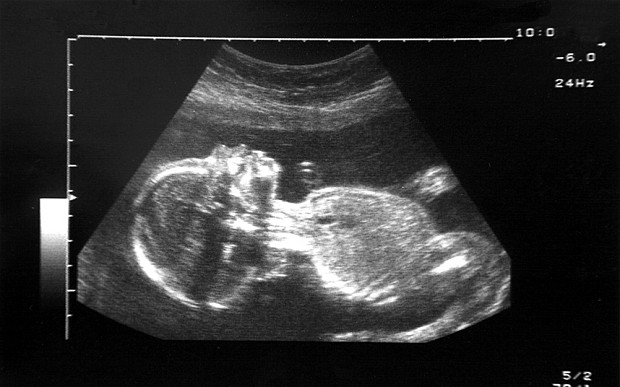

Late-term abortions of fetuses with clefts

Some Members of Parliament in the UK have called for a review of abortion laws since recent data show many more mothers than realized ask that their cleft fetuses be aborted.

According to a committee of MPs and peers, evidence suggests “many pregnancies are being terminated up until full term simply because of cosmetic flaws.”